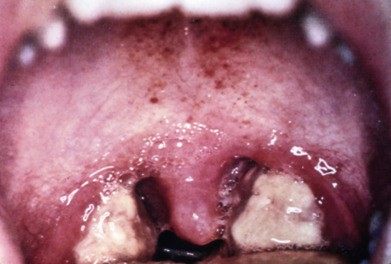

Skin lesion distribution is helpful when distinguishing between common vesicular eruptions, including the grouped localized vesicles and erosions seen in herpes simplex virus, compared with the dermatomal vesicular eruptions secondary to herpes zoster virus. As with other infections, the patient’s underlying immune status also plays a role in the clinical findings, as evidenced by the verrucous herpetic lesions or severe disseminated herpes zoster seen in immunocompromised patients. Other underlying conditions, such as concurrent eczema, can also contribute to the patterns of involvement as seen in eczema herpeticum and the newly coined eczema coxsackium due to Coxsackie virus A6. Obtaining viral cultures and polymerase chain reaction specimens from these lesions is a common way to establish the exact cause of many vesicular viral eruptions.